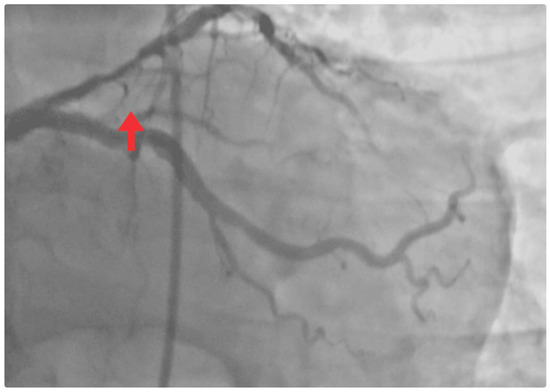

| 8 May | Mild retrosternal chest pain, absence of dyspnea, and improved ventilatory mechanics. | - | - | Coronary angiography: critical proximal LAD stenosis (>90%). Chronic atherosclerotic disease in the circumflex artery, without significant obstructive lesions. Percutaneous coronary intervention (PCI): angioplasty + drug-eluting stenting in the proximal LAD (TIMI 3 flow). |